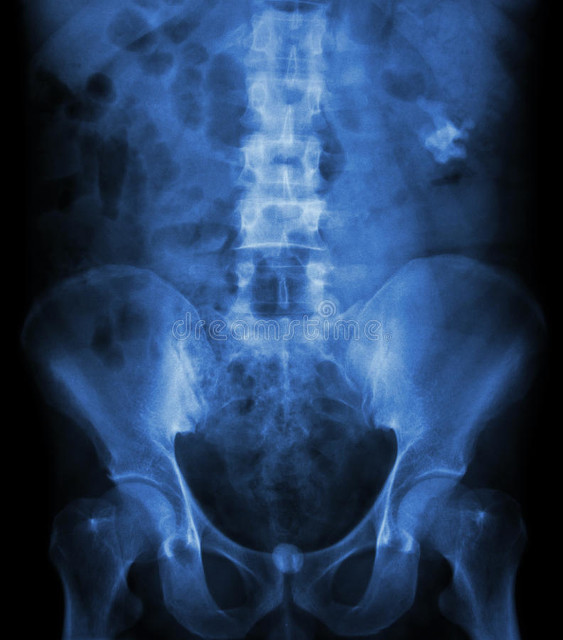

2. 泌尿系B超+腹部平片

3.曾经的金标准“静脉泌尿系造影”敏感性64%变迁为→“金标准”泌尿系CT平扫:通过泌尿系CT平扫不仅可以鉴别诊断结石,而且可以清晰判断结石位置、结石形态大小多少、结石脆性及梗阻程度、包裹可能、感染可能等。